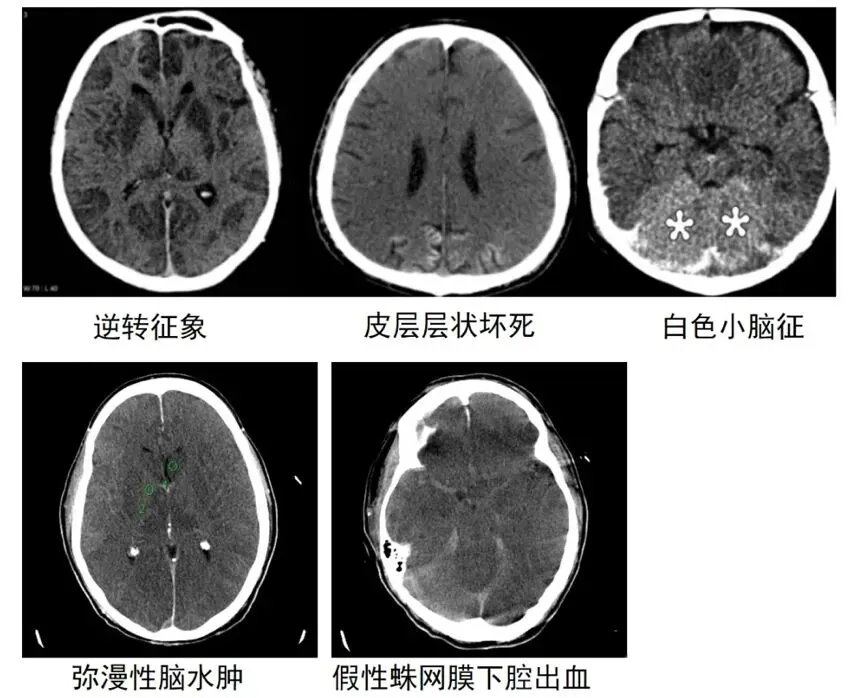

弥漫性脑水肿

脑室变小,脑沟脑裂变窄,脑灰白质分男不清或消失。

逆转征象

正常灰白质的CT值逆转,少数患者在24小时内可见。这一征象是由于弥漫性脑水肿引起颅内压增高,从而深部髓质静脉部分流出受阻扩张所致。

白色小脑征

有研究认为这属于逆转征象的一部分,由于大脑半球存在弥漫性水肿密度减低,导致小脑和脑干呈相对高密度,这一征象的出现表明脑损伤严重且预后不良。

皮层层状坏死

灰质结构上分6层,其中第3层最易受缺血缺氧损害,表现为皮质的线样高密度影,是在大脑氧气和葡萄糖的供应不足的情况下,选择性神经元坏死以满足区域需求。

假性蛛网膜下腔出血

脑水肿和颅内压增高导致脑实质密度减低,而静脉结构充血扩张,从而出现蛛网膜下腔似出血的高密度影。在20%心肺骤停后的患者中可发生,通常在复苏后3天内,表明严重的脑损伤提示预后不良。

迟发性白质脑病

表现为深部白质低密度。

脑萎缩

慢性期可见脑室扩大,脑沟脑裂增宽。